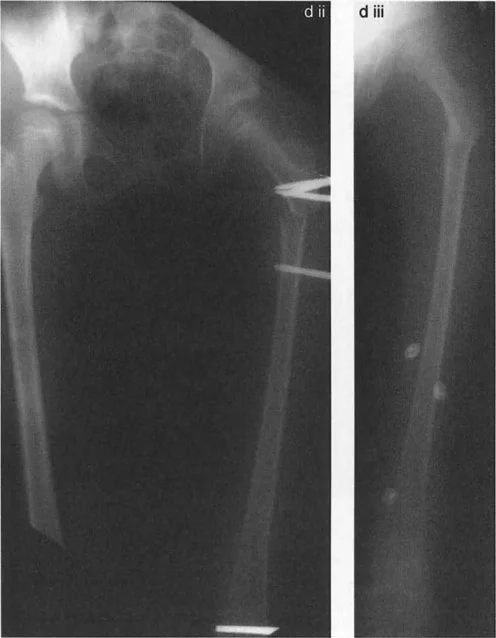

جراحة عظم الفخذ الفحجاء (Valgus Osteotomy) لتصحيح الورك الفحجاء (Varus Deformity)

تُجرى هذه الجراحة عندما يكون عنق الفخذ مائلاً جدًا للأسفل (الورك الفحجاء). تهدف العملية إلى زيادة زاوية عنق الفخذ، مما يجعلها أكثر عمودية.

جراحة عظم الفخذ الروحاء (Varus Osteotomy) لتصحيح الورك الروحاء (Valgus Deformity)

تُجرى هذه الجراحة عندما يكون عنق الفخذ مائلاً جدًا للأعلى (الورك الروحاء). تهدف العملية إلى تقليل زاوية عنق الفخذ، مما يجعلها أكثر أفقية.

اعتبارات تحديد مستوى قطع العظم

يعد اختيار مستوى قطع العظم (Osteotomy Level) أمرًا حاسمًا ويؤثر على جوانب عديدة، بما في ذلك توتر وتر العضلة القطنية الحرقفية (Psoas Tendon) ومسافة القطع عن مركز دوران الزاوية (CORA).

• مستويات القطع: يمكن أن يكون القطع فوق المدور الصغير (Intertrochanteric) أو تحته (Subtrochanteric).

• لذلك، يفضل الأستاذ الدكتور محمد هطيف إجراء جراحة عظم الفخذ الروحاء فوق المدور الصغير، وجراحة عظم الفخذ الفحجاء تحت المدور الصغير، لتحسين النتائج وتسهيل الجراحة.